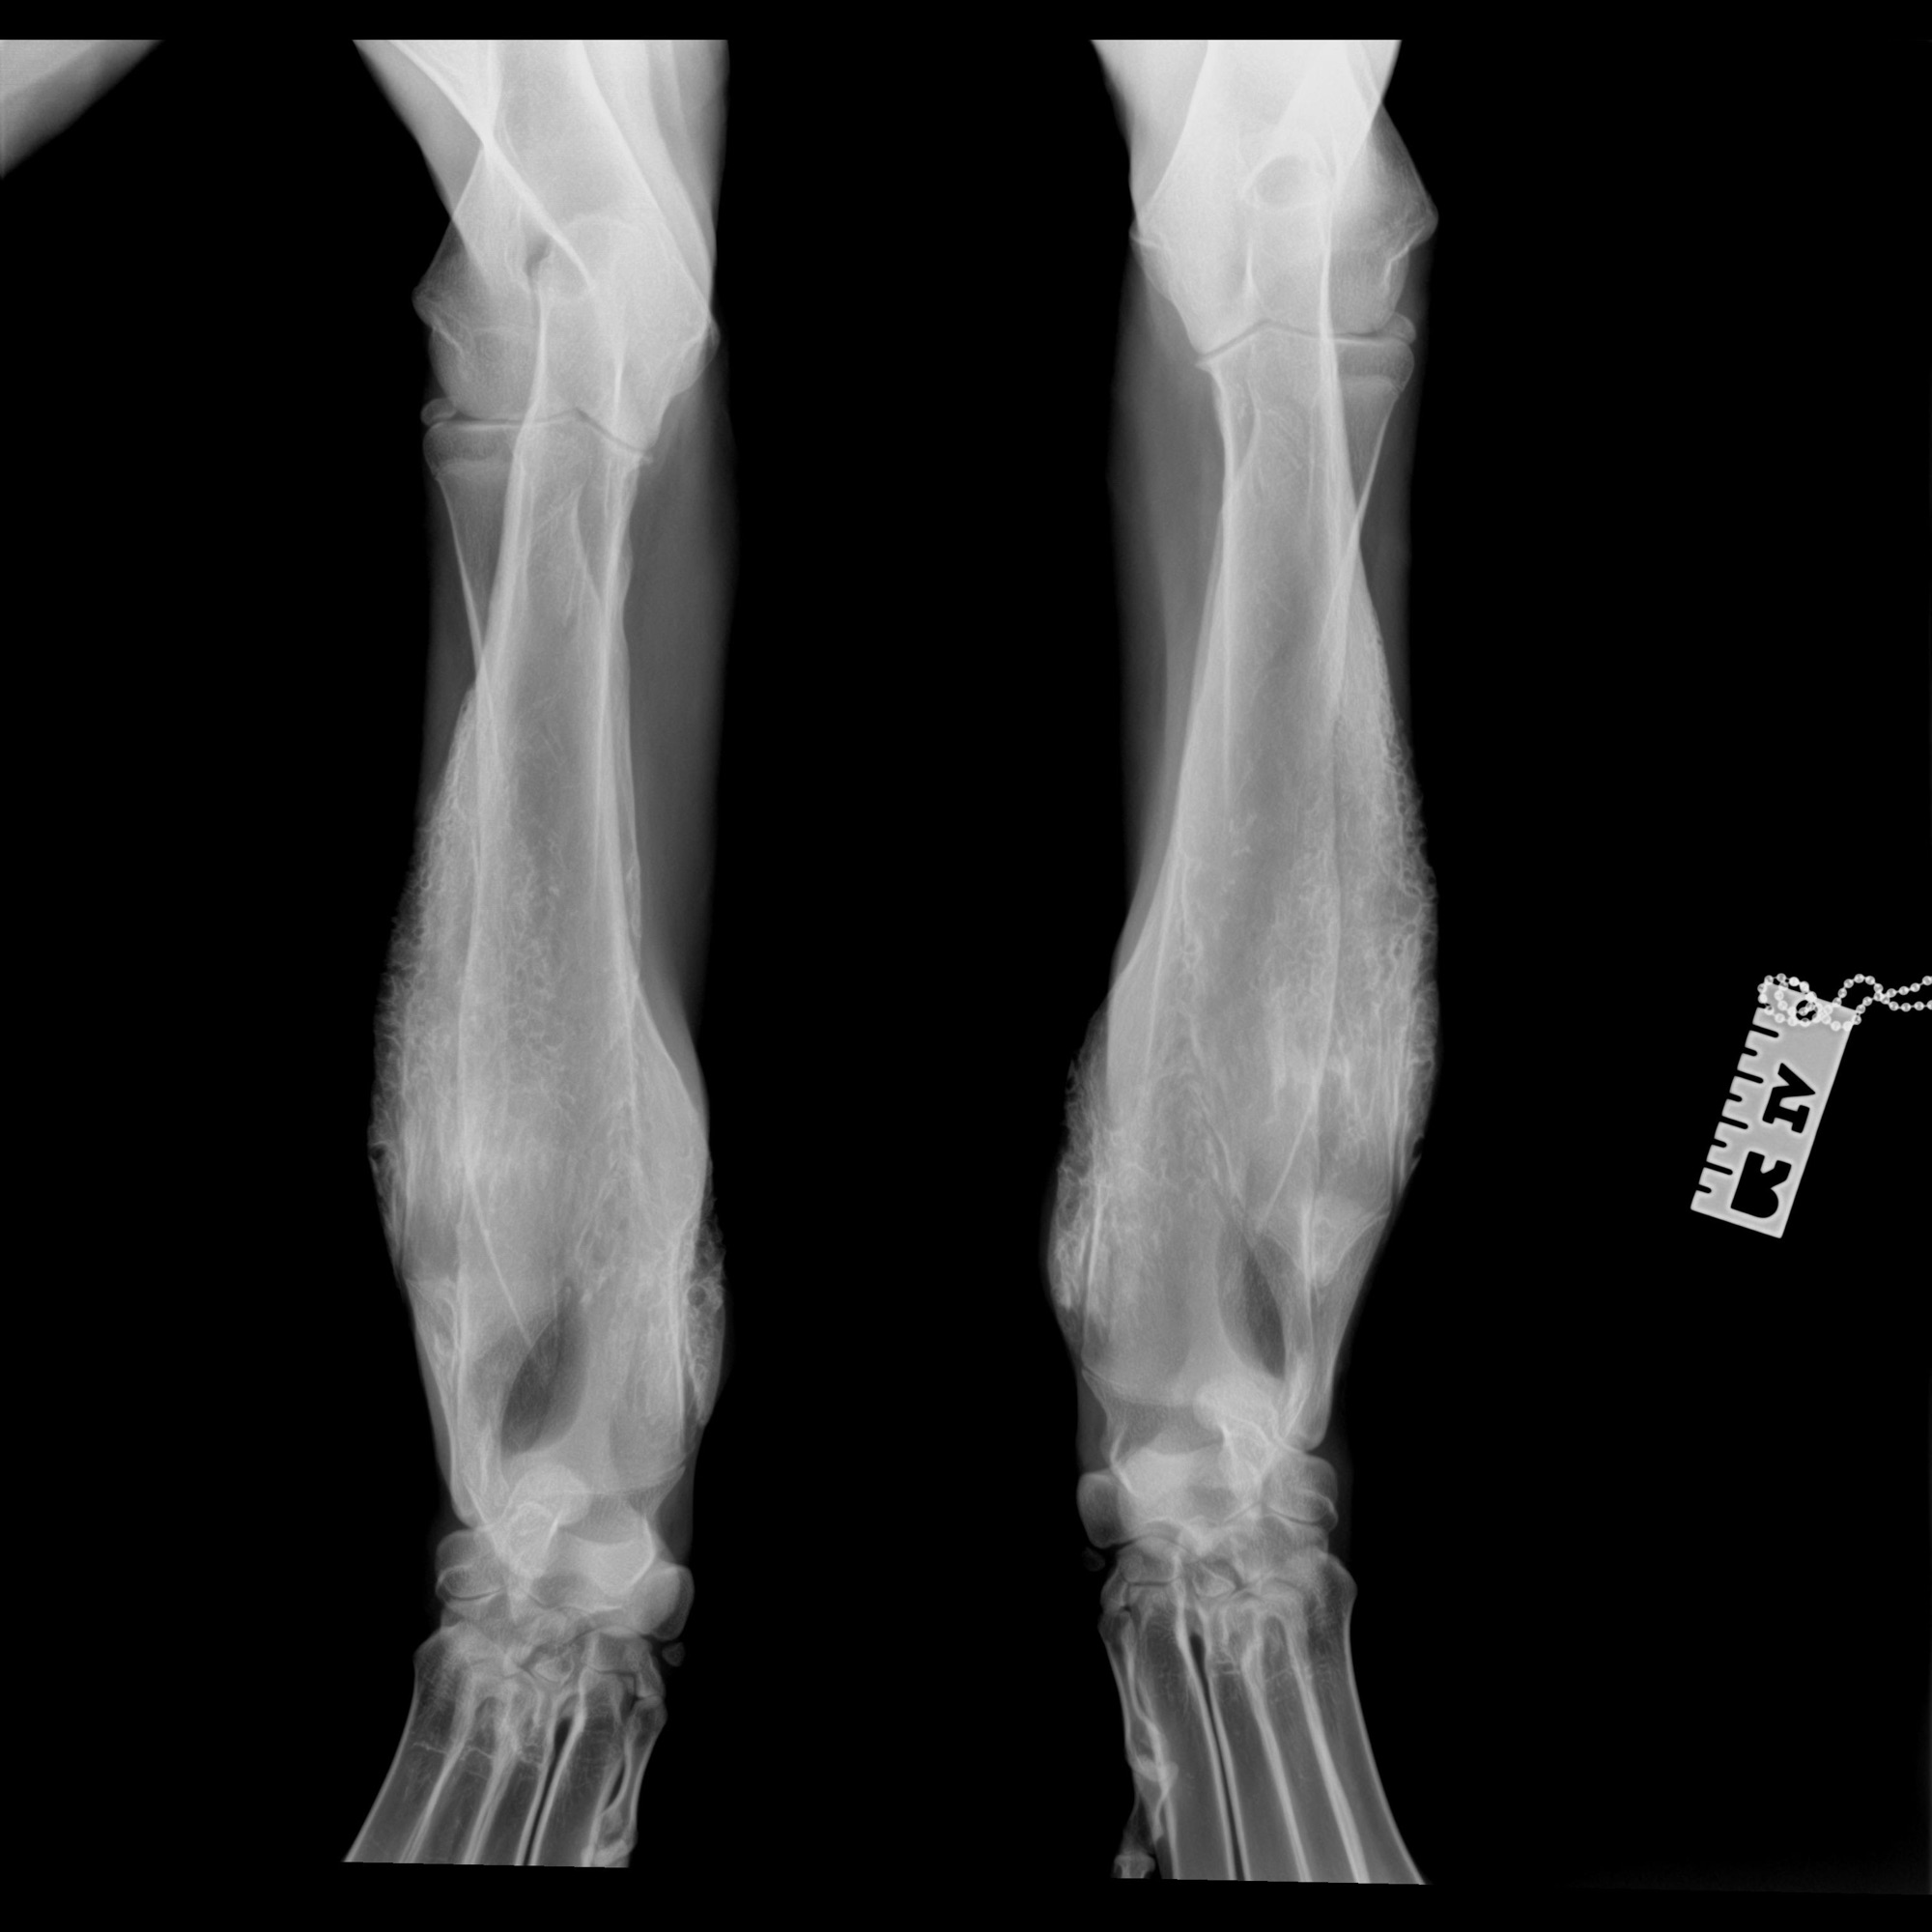

Meet Fred. We are estimating him to be about a year old (DOB 7/1/24). Fred came to us in extremely poor shape in part due to an uncommon disease, craniomandibular osteopathy (CMO). CMO caused extra bone growth in Fred skull and mandible as well as his front legs. He does have signs of CMO in other limbs as well however they are not as prolific as his skull/mandible and front legs.

Fred was vetted at The University of Florida and they confirmed his condition after a CT scan and full body radiographs.